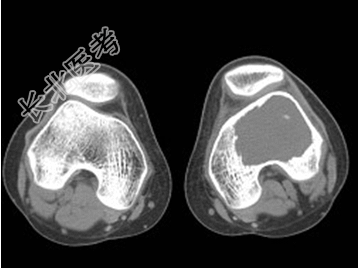

- [材料题] 患者,男,33岁,左股骨肿块半年余,无明显症状,查体一般情况良好。

- 简答题1、结合所提供的图像,该患者诊断为?

- 1、该患者诊断是?2、该疾病的治疗原则是